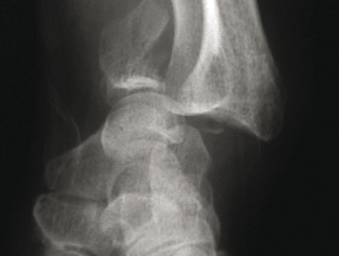

Fracture marginale antérieure

© Henry Coudane, Frédéric Éloy (La Revue du Praticien)

Fracture articulaire.